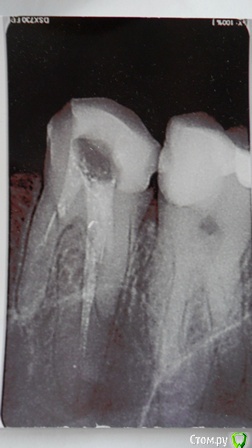

Татьяна-spb Опубликовано 14 июля, 2015 Поделиться Опубликовано 14 июля, 2015 (изменено) Добрый день! Лечила пульпит (4-ка верхняя,справа) в частной клинике-пролечили,запломбировали каналы гуттаперчей,через три дня встала утром с грандиозным отеком с правой стороны(включая глаз),обратилась в стоматологию в доме где живу и делала металлкерамику,стоматолог дала полоскание с прополисом , пролеченный зуб распломбировала,сделала снимок,отправила домой,отек на следующий день спал немного,боли усилились,в пятницу при повторном осмотре была обнаружен периодонтит(гранулема) и одновременно пульпит в 6-ке под металлкерамической коронкой(зуб не был депульпирован),коронку сняли,корни прошли,лечат периодонтит,предложили сделать сложную конструкцию- восстановить 4-ку и 6-ку композитом на штифтах,поставить микропротез на стекловолокне вместо отсутствующей пятерки.Врач из стоматологии в доме озвучил, что диагноз пульпит в 4-ке первоначально был неверен,настаивает на классическом периодонтите,частная стоматология,где этот пульпит лечился, прислала контрольный снимок после пломбировки каналов и предполагает что обострение в 4-ке -это аллергическая реакция на йодосодержащий препарат,используемый при ее лечении.Протезист,поставивший металлкерамику 8 месяцев назад на живую 6-ку, говорит что депульпирование живых зубов под металлкерамику обязательным не является, а природа кист вообще не изучена,потому к образованию периодонтита он отношения не имеет.Помогите разобраться в этой адской пляске стоматологов.http://s015.radikal.ru/i333/1507/c5/c7accc6998da.png Изменено 14 июля, 2015 пользователем Татьяна-spb Ссылка на комментарий

shishok Опубликовано 14 июля, 2015 Поделиться Опубликовано 14 июля, 2015 Коллеги,мне кажется или на контрольном(маленьком) снимке 4-ки имеется трещина корня? Ссылка на комментарий

anvladd Опубликовано 14 июля, 2015 Поделиться Опубликовано 14 июля, 2015 Коллеги,мне кажется или на контрольном(маленьком) снимке 4-ки имеется трещина корня?кажется. Ссылка на комментарий